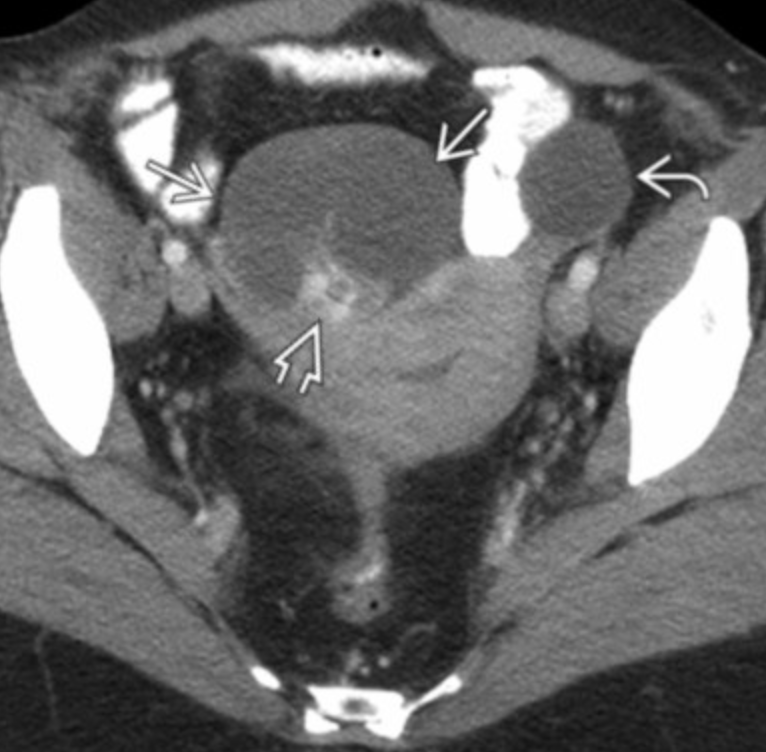

Hyperreactio Luteinalis

• Very similar to ovarian hyperstimulation syndrome

• Bilateral enlarged multicystic ovaries

• WILL HAVE ELEVATD HCG

• Associated with molar pregnancy

• Benign and will resolve with delivery of normal pregnancy or removal of the molar pregnancy in cases of molar pregnancy